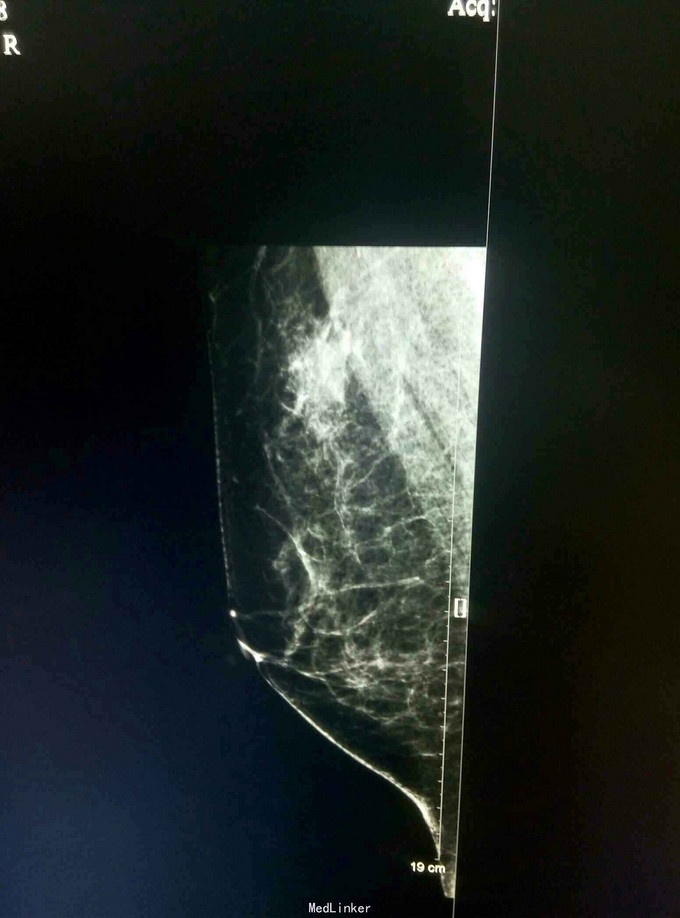

患者,女,50岁,体检发现右乳肿物1月

查体:体格检查未触及明显肿物 辅助检查:彩超钼靶如图所示

诊断:右乳纤维瘤? 治疗:局麻下行右乳肿物切除活检术,术后病理示:右乳肿物符合血管肉瘤样变。经汇报讨论,采取全乳切除加腋窝淋巴结清扫,术后可考虑放疗。